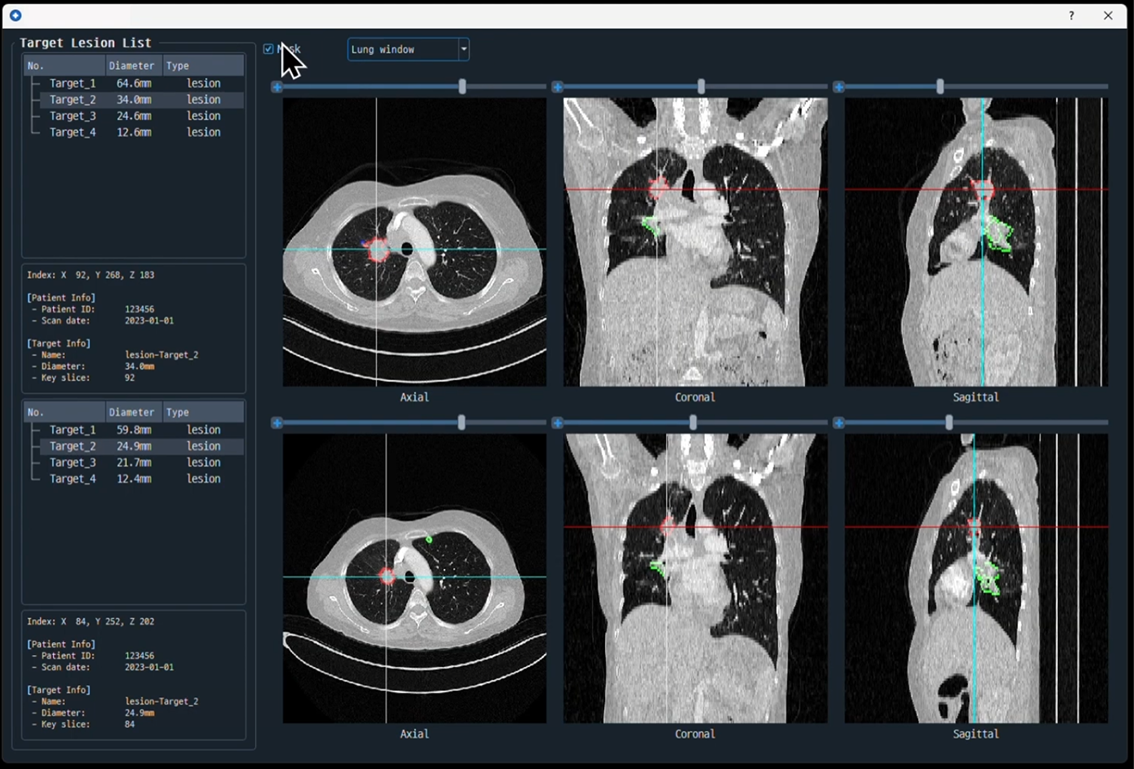

- 진단 자동화 지원 (RECIST & Segmentation)

폐암 진단 추적을 위한 RECIST 가이드라인 자동화 및 3D 디지털 트윈 솔루션과 연동하여, 의료진에게 데이터 기반의 직관적인 리포트를 제공합니다. - 의료 논문 키워드 자동 추출 및 분석